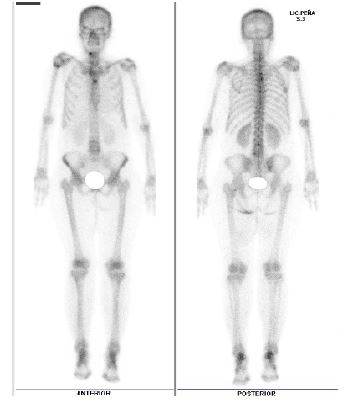

En las Figuras 2 y se aprecia la diferencia entre incluir la medida del pie y omitirlo, observándose que la primera tiene una mejor resolución y visualización de todas las estructuras óseas, facilitando una evaluación correcta para un diagnóstico gammagráfico más preciso.

Figura 2. Se incluyó la medida del pie al adquirir la imagen de cuerpo entero, se aprecia adecuadamente ambos pies.